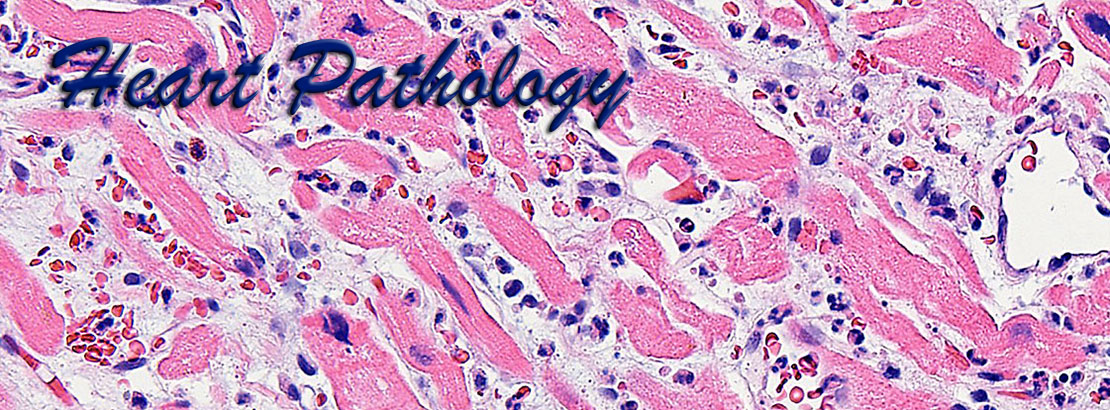

Cardiac pathology is an important area of pathology but is not comprehensively taught at many medical centers due to the paucity of cardiac specimens outside of the autopsy services. Our website uses high definition images obtained from gross pathology specimens and histological slides, both at a resolution of 1800x1350 pixels. Most images have been obtained using Olympus digital cameras.

The images presented here represent a wide variety of heart pathology cases, including acquired diseases, transplantation pathology, idiopathic diseases, tumor pathology, etc., and are accompanied by brief morphological descriptions. The histological images are shown at different optical magnifications and include conventional stains such as hematoxylin-eosin, PAS, trichrome stains, as well as immunohistochemical stains. Also included are some images from normal tissues and from positive and negative controls for the corresponding special stains.